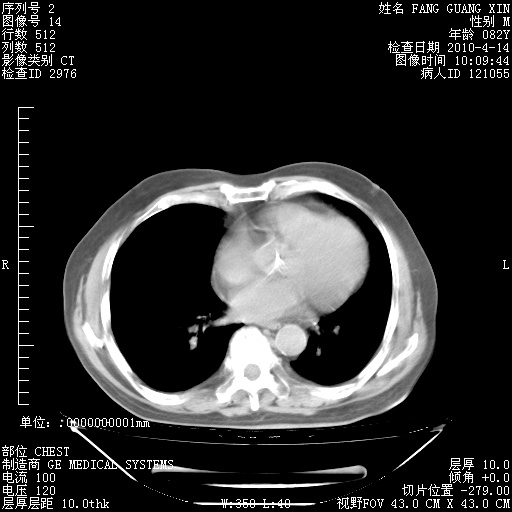

4月14日肺部CT

楼主| 发表于 2010-4-28 16:51 | 显示全部楼层

楼主| 发表于 2010-4-28 16:53 | 显示全部楼层

肺部CT平扫未见异常。